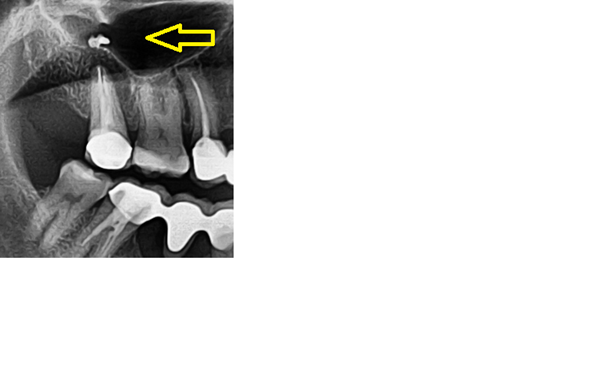

Elemento extraño en radiografía dental

Estoy muy preocupado por el cuerpo extraño que aparece marcado con una flecha amarilla. Les agradeceria enormemente me indicaran que puede ser. Muchas gracias.